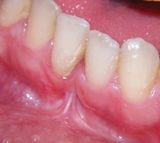

- Chirurgia mucogengivale

- Gengivectomia-gengivoplastica

- Parodontologia

Applicazioni Cliniche